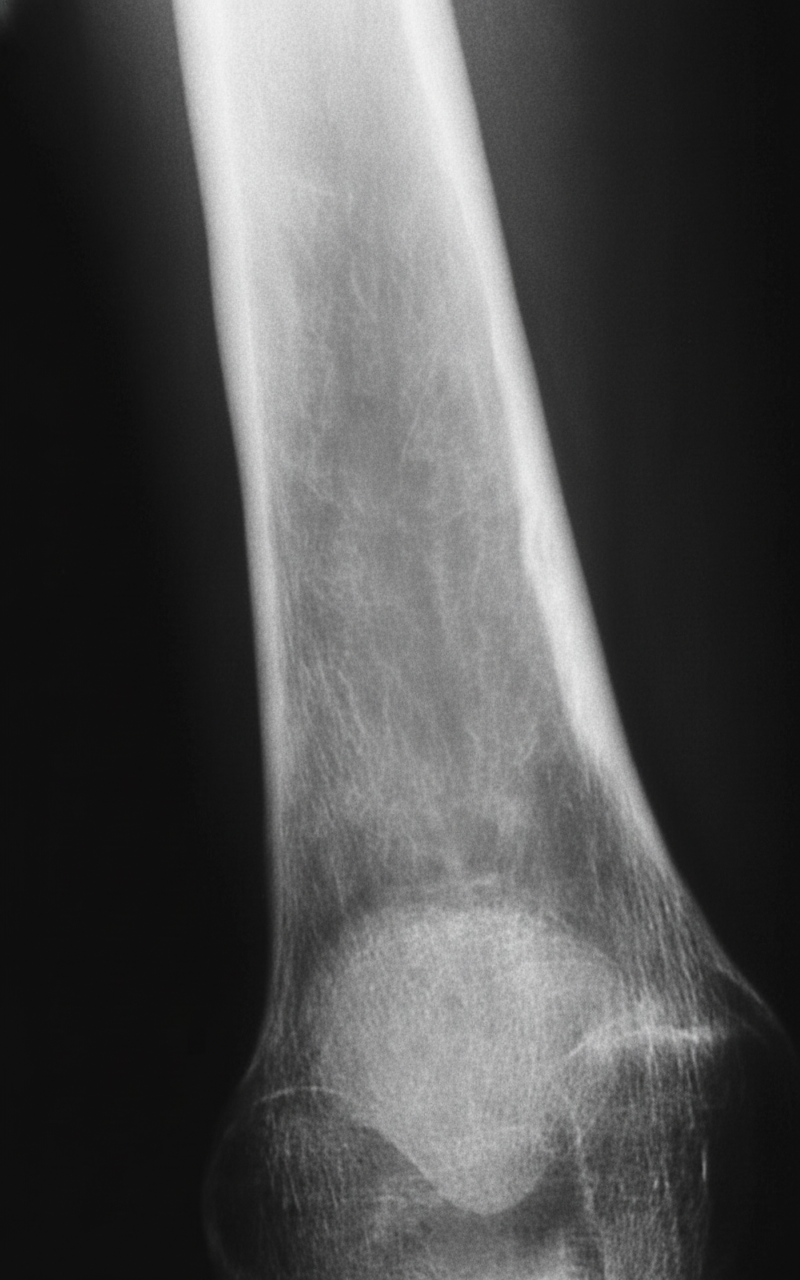

What diagnosis is suggested by the findings on this anteroposterior radiograph of the right tibia?

Explanation: ***Marrow hyperplasia*** - Characterized by **widened medullary cavity** and **thinned cortex** on radiographs, commonly seen in **hemolytic anemias** like sickle cell disease or thalassemia. - Shows **coarsened trabecular pattern** due to increased **erythropoietic activity** expanding the bone marrow space. *Ewing's sarcoma* - Presents with **aggressive permeative bone destruction** and characteristic **onion-skin periosteal reaction** on radiographs. - Typically shows a **soft tissue mass** with bone destruction, not marrow expansion patterns. *Osteomalacia* - Characterized by **Looser zones** (pseudofractures) and **generalized osteopenia** due to **vitamin D deficiency** or phosphate disorders. - Shows **delayed mineralization** and **bowing deformities**, not medullary cavity widening. *Polyostotic fibrous dysplasia* - Demonstrates **ground-glass appearance** with **well-defined sclerotic margins** and **shepherd's crook deformity** in proximal femur. - Shows **fibrous tissue replacement** of normal bone, creating characteristic **cystic lesions** with expansion.